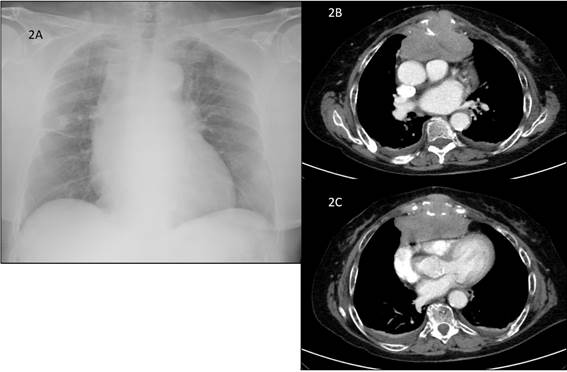

Se realizó una radiografía del miembro inferior izquierdo que mostró una lesión osteolítica de 51 por 22 mm en el tercio medio del fémur, de bordes irregulares y que destruía la cortical (Figura 1A). En el tercio superior y la pelvis se observaban otras lesiones osteolíticas de menor tamaño (Figura 1B). La radiografía de tórax mostraba una cardiomegalia con ensanchamiento mediastínico y redistribución vascular (Figura 2A). En la analítica se objetivó una anemia con hemoglobina de 8,1 g/dl, aumento de proteínas 11,1 g/dl, LDH 1212 UI y calcio 10,4 mg/dl. Además, presentaba un deterioro de la función renal, con una creatinina de 1,52 mg/dl y un filtrado glomerular de 31 ml/min/1,73m2. Se decidió ingreso hospitalario para completar estudio.

Los perfiles hepático y lipídico eran normales. Los marcadores tumorales fueron negativos (AFP, CEA, Ca 125, Ca 15.3 y Ca 19.9). En el proteinograma se objetivó un pico monoclonal kappa de 5,02 g/dl con Ig G de 6060 mg/dl y B2-microglobulina de 8,73 ng/ml. La tomografía tóraco-abdominal mostró una lesión lítica ósea en el cuerpo esternal con una gran masa de partes blandas, heterogénea, de 40 x 94 mm, que invadía el mediastino anterior, ejerciendo un efecto de masa sobre las cavidades cardiacas derechas que provocaba una dilatación del tronco de la arteria pulmonar sugiriendo cierto grado de hipertensión pulmonar (Figuras 2B-2C). Así mismo, describe múltiples lesiones óseas, en su mayoría líticas en ambas palas iliacas, isquion, pubis y sacro; algunas con pequeñas masas de partes blandas asociadas. Se realizó un aspirado de médula ósea, en el que se evidenciaron linfocitos maduros y 28-56 % de células plasmática. Los hallazgos confirman el diagnóstico de mieloma múltiple Ig G kappa con múltiples lesiones osteolíticas, algunas compatibles con plasmocitomas, el más importante en el cuerpo esternal que ejerce efecto masa sobre cavidades cardiacas. La anemia, hipercalcemia e insuficiencia renal eran secundarias a la patología hematológica. Se indicó radioterapia urgente sobre la masa mediastínica, un total de 5 sesiones; posteriormente se inició quimioterapia esquema VMP para paciente frágil (bortezomib, melfalan y dexametasona), en un primer momento, sin melfalan, hasta la mejoría de la función renal. Finalmente, se realizó un enclavamiento intramedular profiláctico del fémur izquierdo.

El rol de las imágenes en el MM incluye la evaluación de la extensión de la enfermedad, la identificación y caracterización de las complicaciones como fracturas patológicas o compromiso neurológico1. La radiología convencional sigue siendo el método estándar para evaluar el compromiso óseo, aunque solo permite la identificación de lesiones con destrucción avanzada con un mínimo de afectación del 30 % del hueso trabecular1,3. La radiografía es anormal en el 79 % de los pacientes en el momento del diagnóstico, el 67 % de los casos presentan lesiones líticas y el 20 % tienen osteoporosis, fracturas patológicas o fracturas vertebrales1. Las lesiones radiográficas típicas son líticas y en “sacabocados”. En los huesos planos, como los del cráneo y pelvis, no suele haber esclerosis reactiva en el hueso circundante3. En el caso de los huesos largos, las lesiones pueden manifestarse como festoneado endóstico, lesiones líticas o áreas moteadas por la conjunción de múltiples lesiones pequeñas (Figura 1B), hasta grandes lesiones destructivas3) (Figura 1A). Estas lesiones osteolíticas presentan un tamaño uniforme y unos márgenes bien definidos, siempre son subcorticales y elípticas, y son capaces de coalescer en grandes segmentos de destrucción. Un rasgo característico es una radiolucencia circular de localización subcortical asociada a erosión de los bordes internos corticales3. Hasta el 84 % desarrollarán lesiones esqueléticas en algún momento durante el curso de la enfermedad1. También puede manifestarse como una osteopenia difusa sin lesiones líticas, principalmente a nivel de la columna vertebral. Esta situación facilita la presentación de fracturas por compresión. La tomografía computarizada tiene mayor sensibilidad que la radiografía convencional para detectar lesiones líticas pequeñas1,3. Además, ayuda a planificar la radioterapia y un eventual procedimiento quirúrgico. La resonancia magnética es la técnica de elección para la evaluación de la columna vertebral en pacientes con MM asintomáticos o con clínica de compresión medular o radicular1. Tiene una sensibilidad del 92 % para la detección de lesiones líticas en columna lumbosacra, siendo superior a cualquier otro método de imágenes1. La tomografía de emisión de positrones es una imagen de tomografía nuclear que utiliza radiofármacos marcados como la fluorodesoxiglucosa (FDG) que identifica a las células tumorales debido a su elevada tasa metabólica y alta demanda de glucosa3. Posee una sensibilidad del 72 % para detectar compromiso óseo, aunque es menos eficiente para identificar lesiones en el cráneo, debido a la alta captación fisiológica del trazador en el cerebro adyacente1. Su principal ventaja es la capacidad de distinguir entre mieloma activo (FDG positivo) y la gammapatía monoclonal de significado inespecífico o enfermedad latente. Finalmente, tanto la densitometría ósea como la gammagrafía con tecnecio no son recomendadas en la evaluación del MM1,3.

Pueden presentarse plasmocitomas, masas formadas por células plasmáticas monoclonales que aparecen tanto en el hueso como en los tejidos blandos y se asocia con enfermedad sistémica. Rara vez son hallados en la pared torácica y su localización esternal, como en nuestro caso, es excepcional5.